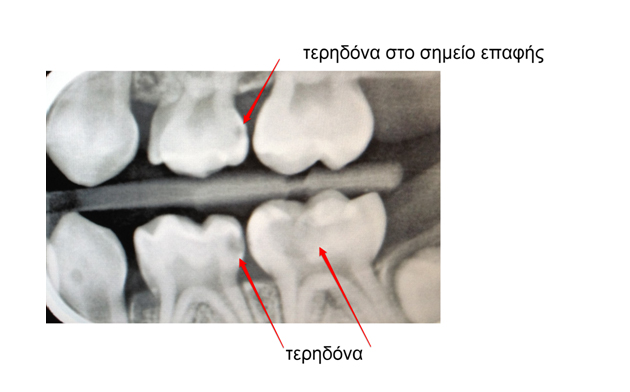

Στο ιατρείο μας, κάνουμε σφραγίσματα στα παιδικά και μόνιμα δόντια στο χρώμα του δοντιού, θυσιάζοντας όσο το δυνατόν λιγότερο οδοντικό ιστό. Μάλιστα, επειδή με τον ακτινογραφικό έλεγχο εντοπίζουμε τις τερηδονικές βλάβες σε αρχικό στάδιο, προλαβαίνουμε η τερηδόνα να μην προχωρήσει πολύ και βλάψει τον πολφό (νεύρο) του δοντιού.